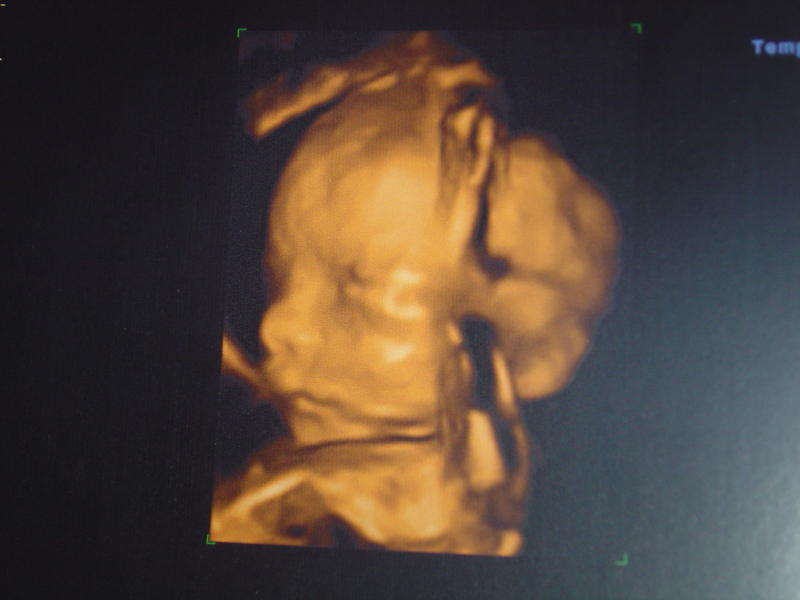

Alors moi écho faite , tout vas bien et c'est ... UNE FILLE !!!!

clélia: félicitation ma belle!! une nénette c'est top!!